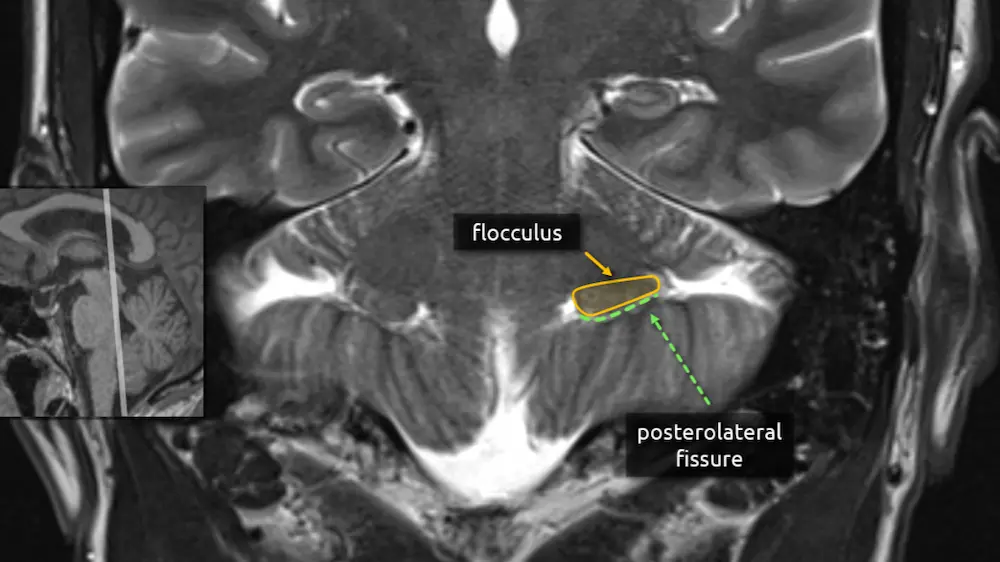

The first step in understanding the cerebellum is to delineate the anterior, posterior, and flocculonodular lobes using the primary fissure and the posterolateral fissure (Figure 2B).

The flocculus is worth recognizing due to its tendency to mimic an extra-axial mass in the cerebellopontine angle (e.g. a vestibular schwannoma) on head CTs when asymmetrically prominent or dense, particularly in the axial plane. See Figure 5. and Figure 6.